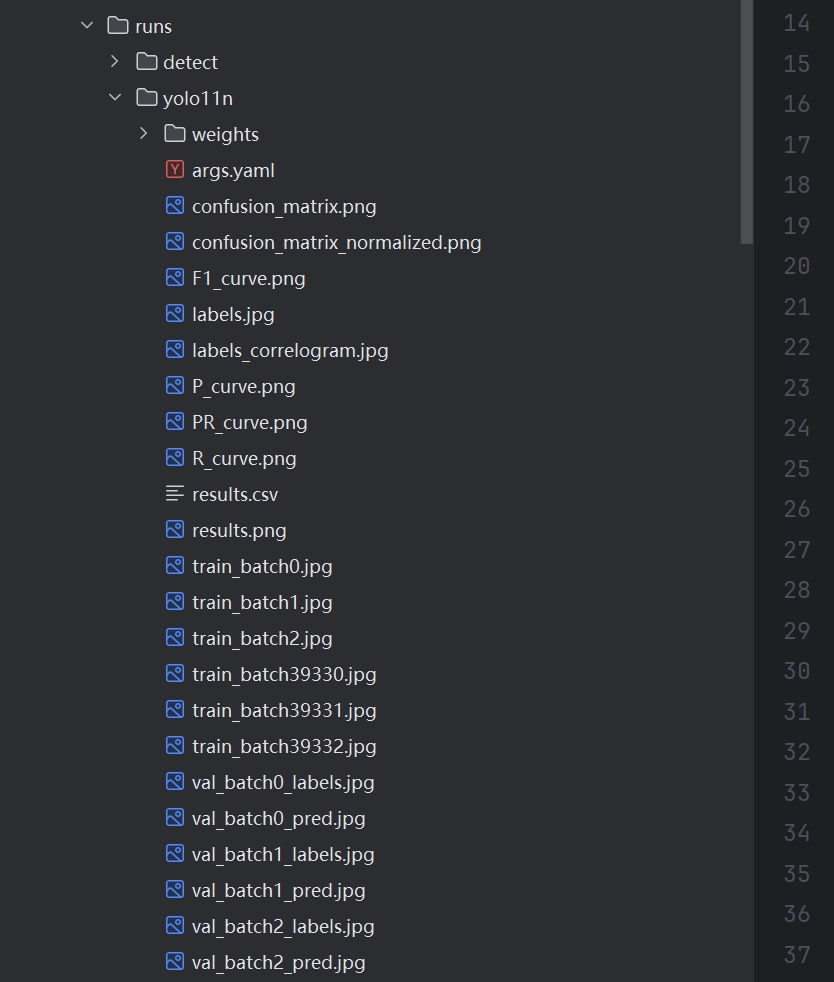

实验结果的指标图均保存在runs目录下, 大家只需要对实验过程和指标图的结果进行解析即可。

如果只指标图的定义不清晰,请看这个位置:YOLO11模型指标解读-mAP、Precision、Recall_yolo11模型训练特征图-CSDN博客

train/box_loss(训练集的边界框损失):随着训练轮次的增加,边界框损失逐渐降低,表明模型在学习更准确地定位目标。

train/cls_loss(训练集的分类损失):分类损失在初期迅速下降,然后趋于平稳,说明模型在训练过程中逐渐提高了对肺结节的分类准确性。

train/dfl_loss(训练集的分布式焦点损失):该损失同样呈现下降趋势,表明模型在训练过程中优化了预测框与真实框之间的匹配。

metrics/precision(B)(精确度):精确度随着训练轮次的增加而提高,说明模型在减少误报方面表现越来越好。

metrics/recall(B)(召回率):召回率也在逐渐上升,表明模型能够识别出更多的真实肺结节。

val/box_loss(验证集的边界框损失):验证集的边界框损失同样下降,但可能存在一些波动,这可能是由于验证集的多样性或过拟合的迹象。

val/cls_loss(验证集的分类损失):验证集的分类损失下降趋势与训练集相似,但可能在某些点上出现波动。

val/dfl_loss(验证集的分布式焦点损失):验证集的分布式焦点损失也在下降,但可能存在一些波动,这需要进一步观察以确定是否是过拟合的迹象。

metrics/mAP50(B)(在IoU阈值为0.5时的平均精度):mAP50随着训练轮次的增加而提高,表明模型在检测任务上的整体性能在提升。

metrics/mAP50-95(B)(在IoU阈值从0.5到0.95的平均精度):mAP50-95的提高表明模型在不同IoU阈值下的性能都在提升,这是一个更严格的性能指标。

当iou阈值为0.5的时候,模型在测试集上的map可以达到68.1%。下面是一个预测图像,可以看出,我们的模型可以有效的预测出这些尺度比较小的交通目标。